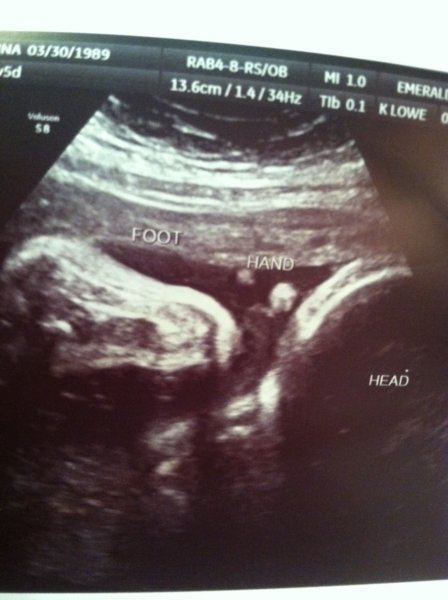

IMG_0295